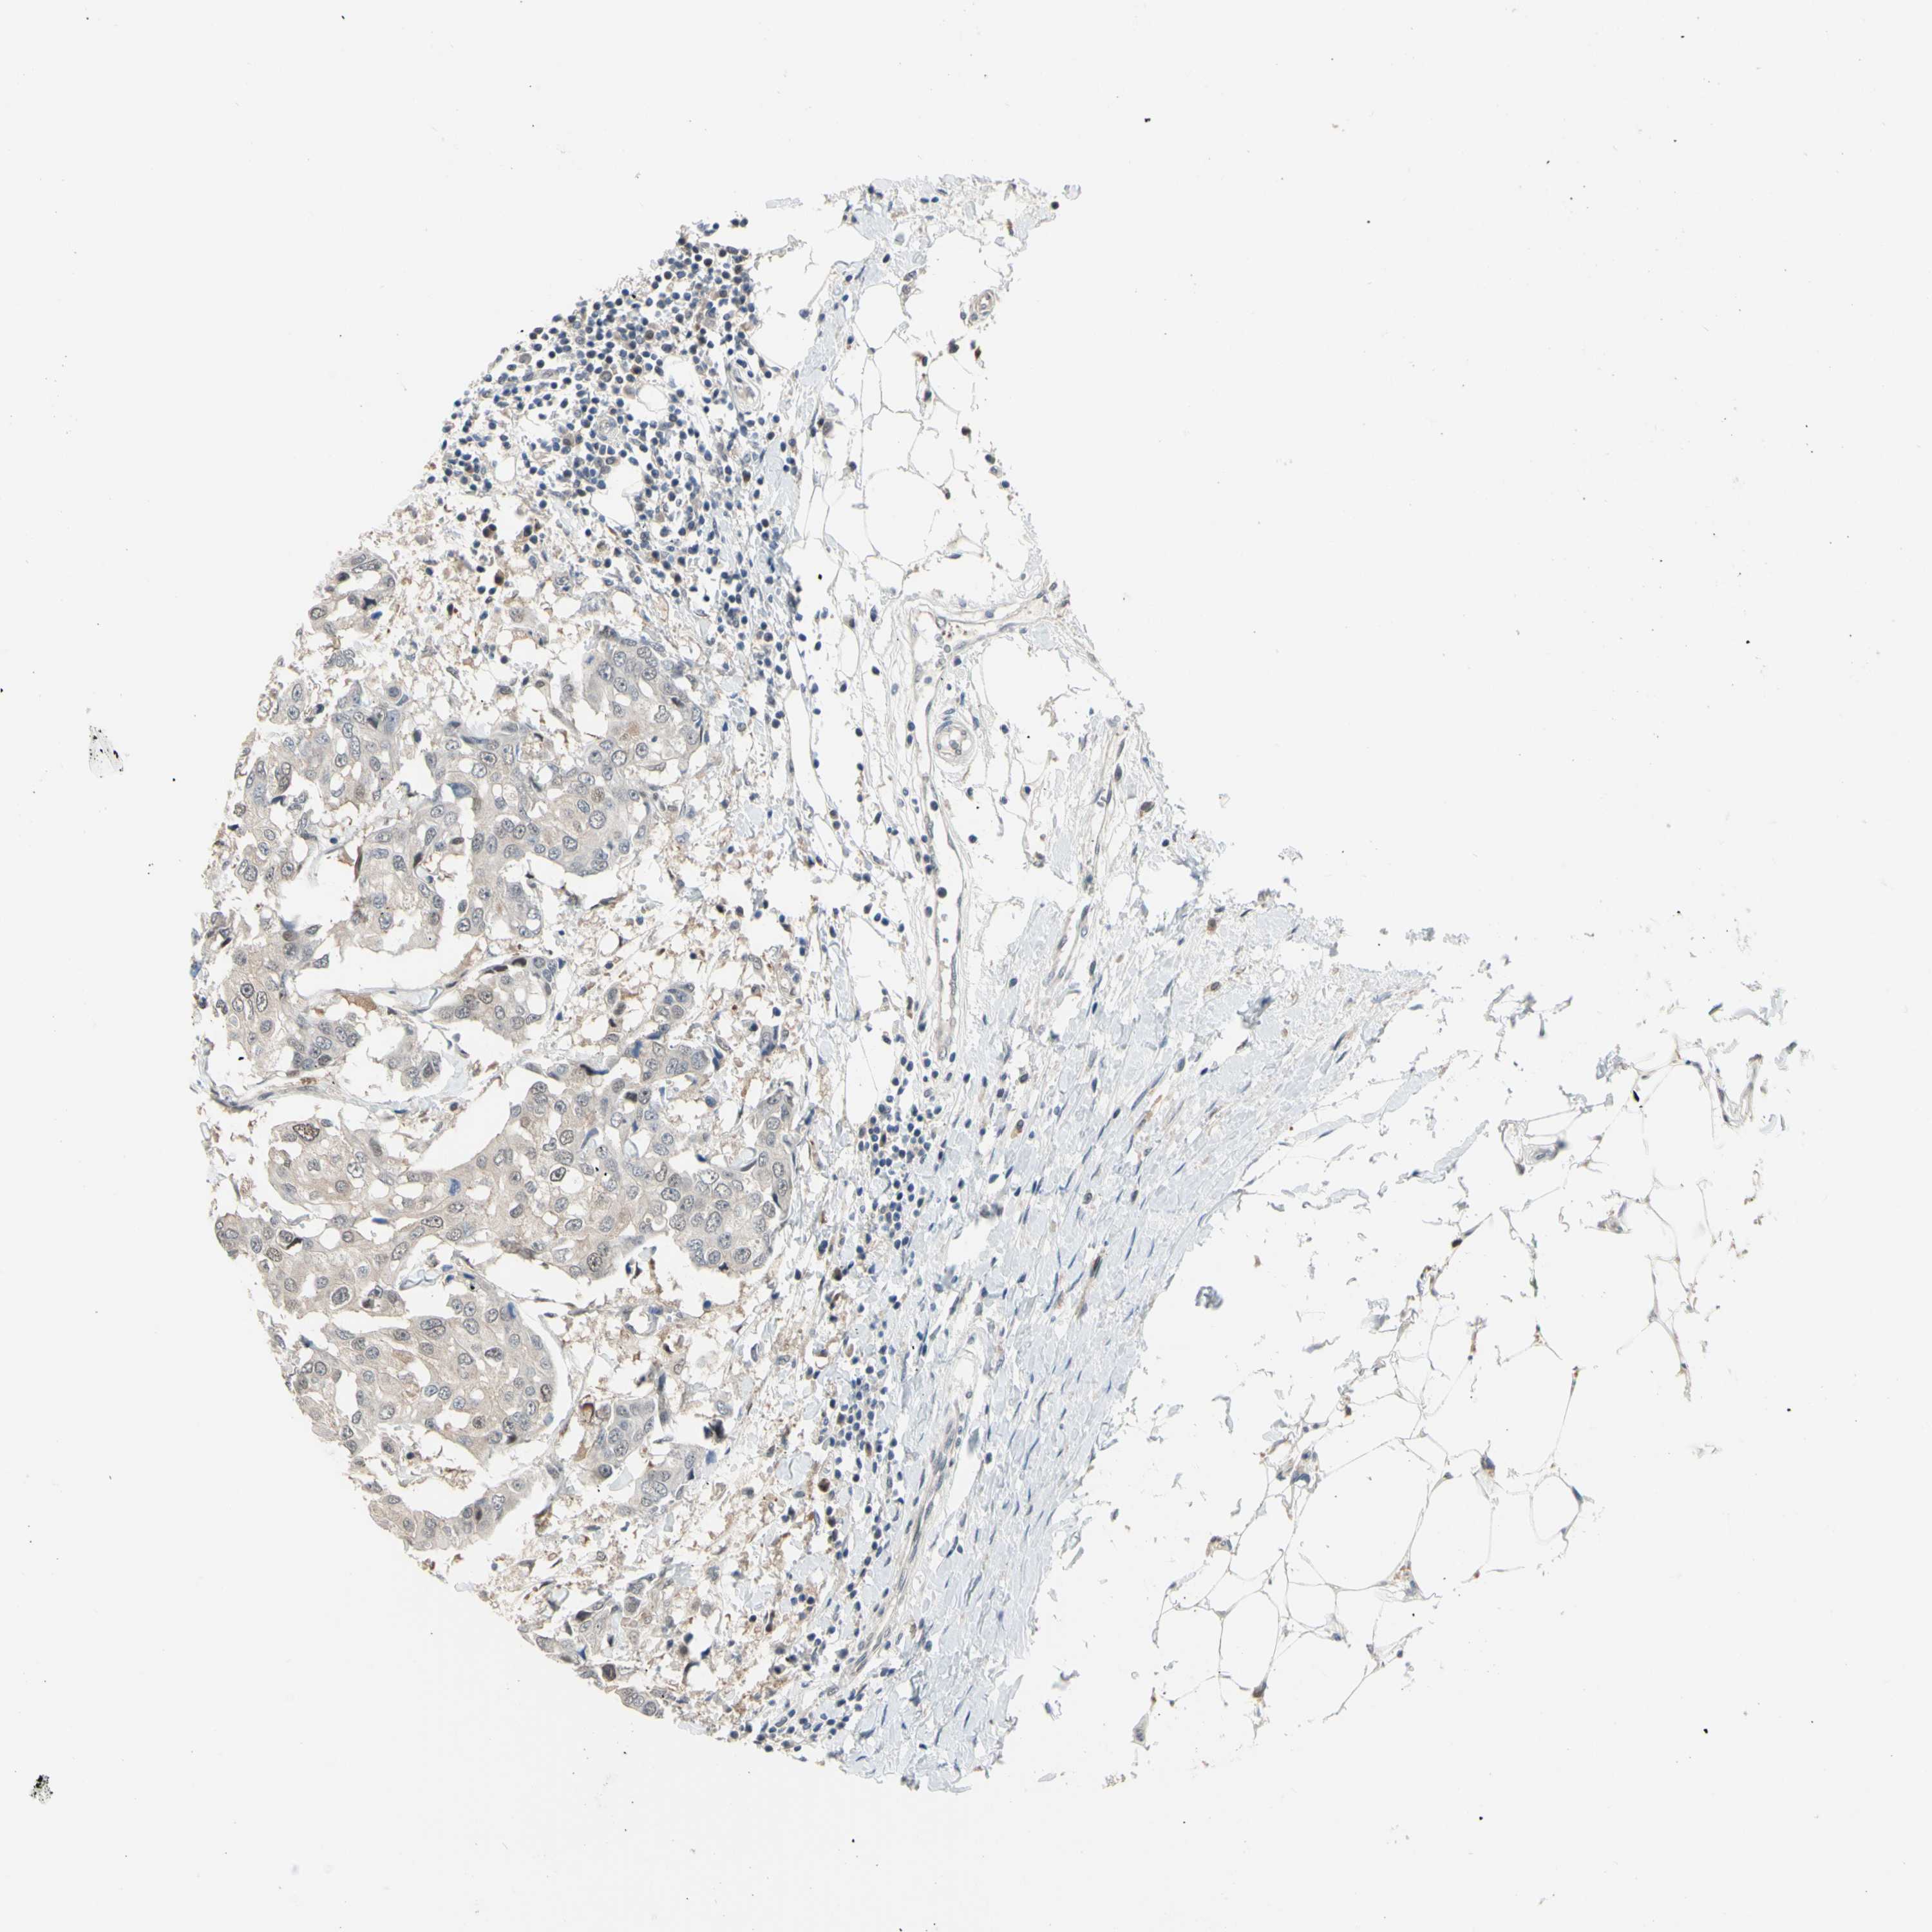

CANCER BREAST CANCER Show tissue menu

BRCA TCGA BRCA VALIDATION PROTEIN EXPRESSION